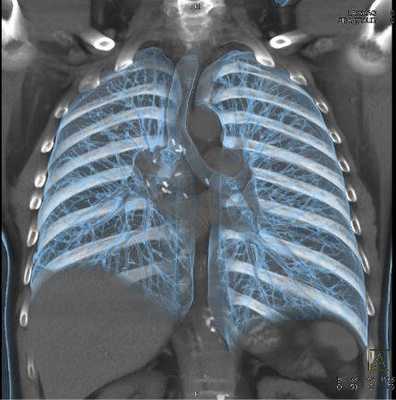

Мультиспиральная КТ грудной клетки, 3D-реконструкция

Специалисты выделяют в средостении три области: центральное (сосудистое пространство с перикардом и его содержимым, сосудами и лимфатическими узлами), переднее (жировая клетчатка, вилочковая железа, внутренние грудные артерии и лимфоидные ткани) и заднее (трахея, пищевод, нисходящая часть грудной аорты, лимфоузлы и паравертебральные пространства грудной клетки). Соответственно, все патологические процессы, которые протекают в данных зонах, могут быть видны.